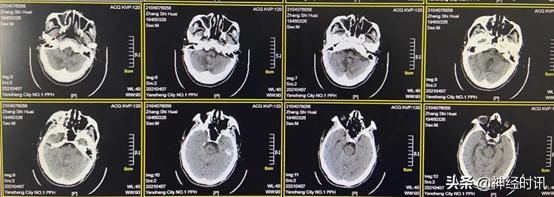

2月8日(脑血疏用药两周半后)复查CT,显示患者小脑血肿基本淡化吸收,量约10 ml,水肿达到高峰,但并未对脑干造成压迫,继续口服脑血疏口服液

2月21日(脑血疏用药1个月后)复查CT,显示患者小脑血肿基本吸收消失,患者神志明显好转,可自主饮食,少量活动,继续服用脑血疏口服液